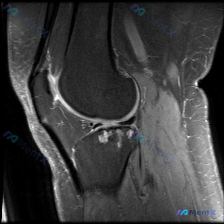

拿到这份踝关节冠状位T2序列MRI,一开始问题问的是有没有软骨异常,我整理了完整读片和分析思路,大家一起看看。 一、先看影像基本信息 这是踝关节冠状位T2加权MRI,我们逐层梳理所有结构的表现: 1. 骨性结构:胫骨、腓骨远端和距骨形态完整,没有明显骨折线,骨髓信号整体尚可,但距骨内部和踝关节周围部...